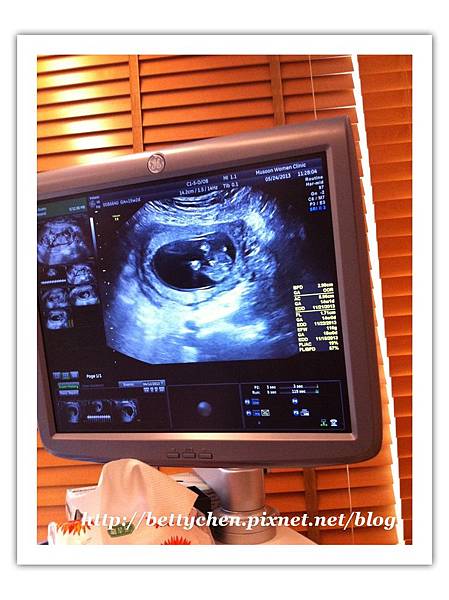

心跳聲正常!!!!週數也正常!!!!!

有跟醫生提過有滑倒的事~~~

醫生說胎兒有羊水保護是還好,怕是怕胎盤出血!!!!

看起來都正常沒事......(呼~~安心了)

小元寶腳還交疊著咧!!!

上次看他的腳就一直狂踢,現在可能長大了空間變小了,哈哈

接下來的圖片可能有點難懂,我有做文字的說明唷^^

小元寶的頭,還有手~~~

李木生的超音波真的超級清楚的!!!!

他的骨骼、手指頭都看得到.....

小元寶的脊椎還有肚子~~~~

脊椎那條白白的超明顯的!!!!